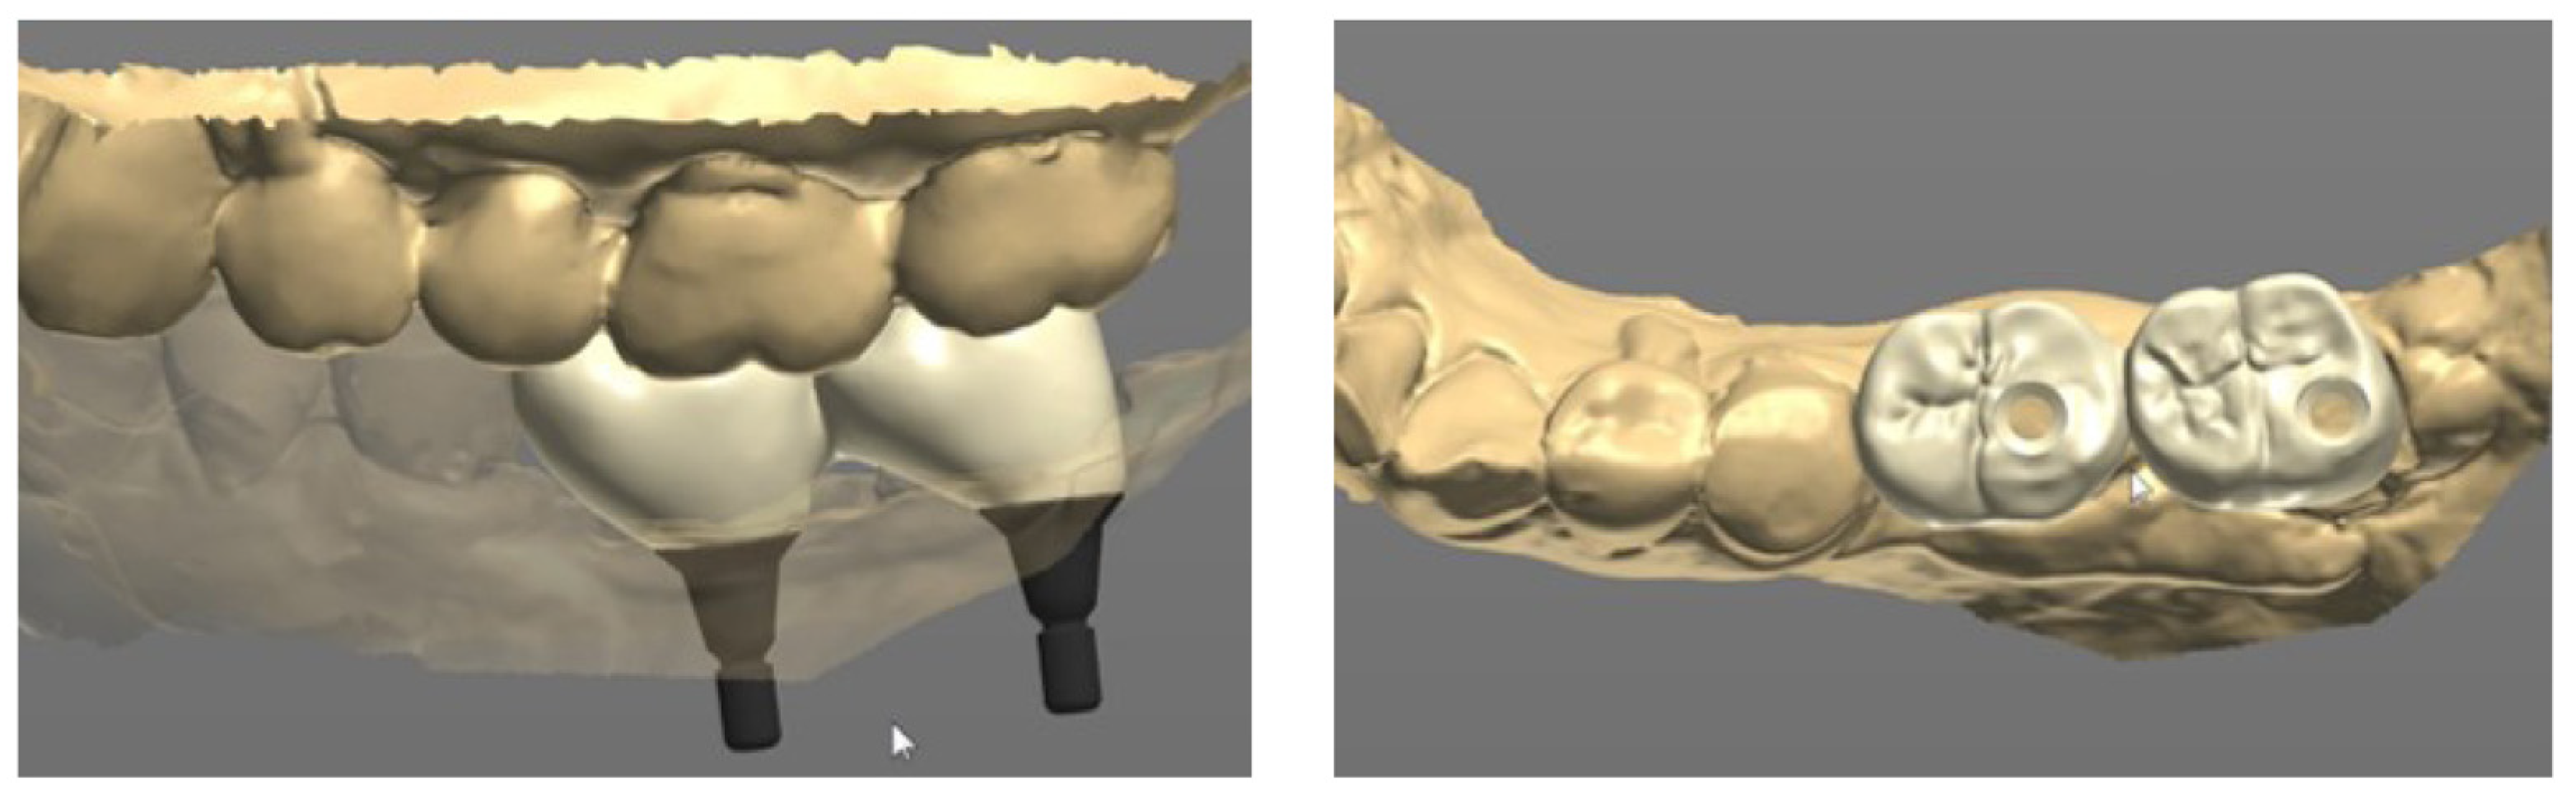

Next, a healing cap was connected to the multi-abutment (Figure 3A). The healing cap served as a normal healing abutment and an impression coping, intended for impression taking through recognition points on the occlusal surface, was also placed. The final impressions were taken using an addition-type silicone impression material (Aquasil LV and XLV; Dentsply Sirona, Milford, DE, USA). In a dental laboratory, the master model obtained from the impression was model-scanned, and the scan data was sent to a computer-aided design (CAD) software program (Trios II; 3Shape, Copenhagen, Denmark) (Figure 3B).

The final prosthesis was designed on a CAD software program through using the scanned information (Figure 4). The prefabricated link with appropriate height and diameter was selected considering the positional relationship between the implant and adjacent teeth and opposing teeth.

Next, the same laboratory process described in case 1 was performed. The prosthesis was designed on the CAD software, and a prefabricated link was selected through the scan data obtained from the model scan (Figure 10). A final prosthesis was obtained by milling zirconia through a CAM milling machine. A prefabricated substructure (link) (Toplan Co., Seoul, Republic of Korea) was fitted to the final prosthesis through frictional force.

Figure 4. Prosthetic design of implant prosthesis on CAD software program.

Figure 10. Prosthetic design of implant prosthesis on CAD software program.